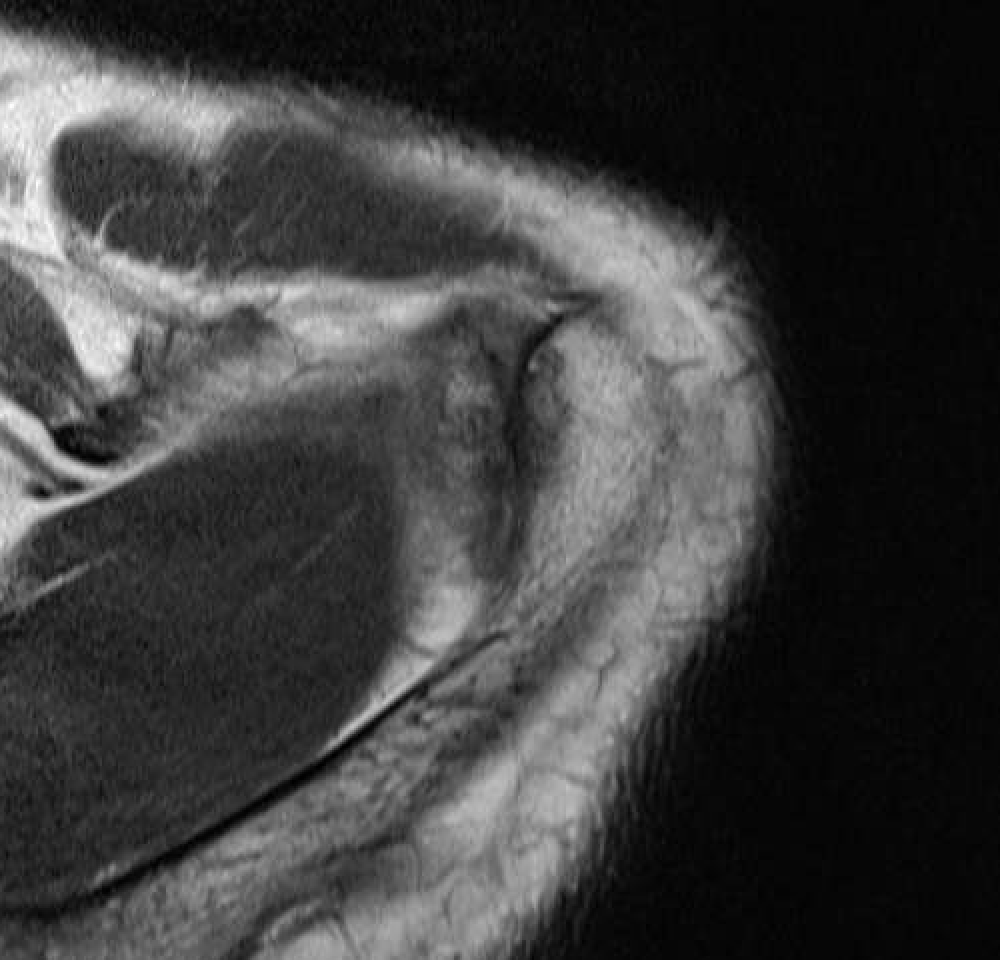

MRI

Acromioclavicular osteoarthritis

Grade I: Normal

Grade II: Capsular distension, bone marrow edema, mild joint narrowing

Grade III: Capsular distension, joint space narrowing, marginal osteophytes

Grade IV: Markedly abnormal ACJ with large osteophytes